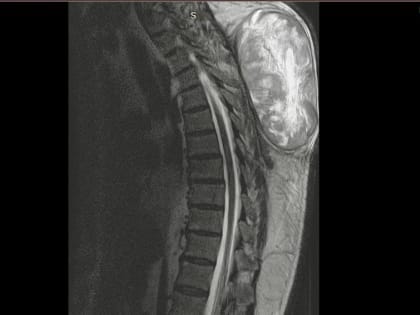

Успешное удаление гигантской опухоли позвоночника в Туле

Медики Тульской областной клинической больницы провели сложную операцию на позвоночнике.

Успешная операция по удалению гигантской опухоли в Туле

Врачи провели сложную операцию на позвоночнике 60-летнего пациента.